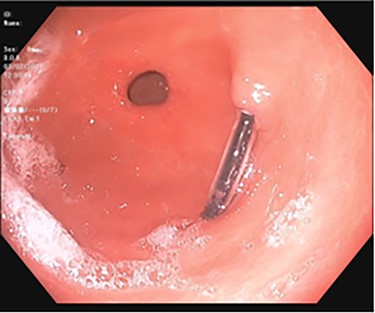

A 43-year-old incarcerated woman with borderline personality disorder and a long history of swallowing various foreign objects in periods of stress presented to the emergency department after swallowing a cup of bleach. Her surgical history was significant for multiple celiotomies for retrievals of purposefully ingested foreign bodies. During evaluation, she also admitted to swallowing an ink pen 3 weeks prior to swallowing the bleach for which she did not seek medical evaluation. She reported no food intolerance or changes in bowel function secondary to swallowing these objects. She presented with mild abdominal pain and cramping, and her vital signs and laboratory investigations were all within normal limits. Her abdominal exam was notable for mild tenderness to palpation diffusely. Computed tomography (CT) of the abdomen (Fig. 4) showed a linear foreign body in the distal gastric antrum penetrating the inferior wall and extending into the adjacent peritoneal fat. No free air or free fluid was appreciated. Initial esophagogastroduodenoscopy (EGD) was significant for mild erythema and edema to the esophageal and duodenal mucosa as a result of the caustic ingestion, and the pen was found to be deeply perforating the stomach antral wall with no associated ulcer or edema (Fig. 1). The depth at which the foreign body was lodged was uncertain, so there was concern for organ involvement outside of the gastric wall. Repeat EGD was done to assess for manifestations of esophageal, gastric or duodenal injuries from her caustic ingestion, and it revealed normal gastric mucosa (Fig. 2). A joint case was planned with the gastroenterology service for endoscopic foreign body retrieval, possible laparoscopic retrieval and gastric repair and possible open retrieval and gastric repair. The patient was taken to the operating room for the third EGD, which revealed spontaneous migration of the foreign body from the perforation site into the lumen of the gastric body (Fig. 3a). Additionally, there was spontaneous closure of the site of previous perforation (Fig. 3b and c). The ink pen was easily removed transorally using an endoscopic snare, and no further surgical intervention was required. After the procedure, the patient reported complete resolution of her abdominal pain and was able to tolerate a regular diet without problems.

EGD on initial presentation; gastric antrum with foreign body perforating through the gastric wall.

Subsequent EGD 3 days later; gastric antrum with foreign body perforating through the gastric wall; normal gastric mucosa after ingestion of bleach.